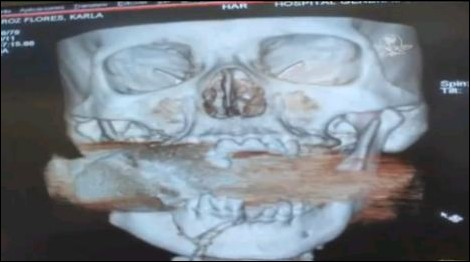

X光掃描圖顯示,一枚手榴彈卡在了弗洛雷斯的上下頜骨之間。

當(dāng)弗洛雷斯醒來時(shí),她已被送到了醫(yī)院。醫(yī)生們一開始還以為弗洛雷斯的臉部受到了石塊的重?fù)簦谶M(jìn)行X光掃描后發(fā)現(xiàn),在她的上下頜骨之間卡著一枚未爆炸的手榴彈。有關(guān)專家判斷,該手榴彈是經(jīng)過發(fā)射器投擲的,一旦被引爆將會危及周圍十米以內(nèi)的人員。